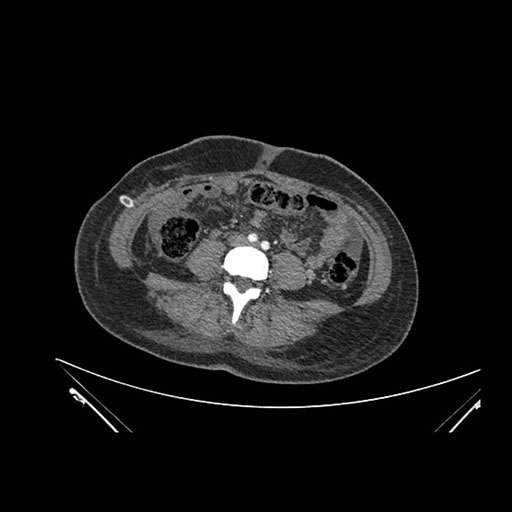

Axial Venous

Imaging analysis

Based on initial findings, which issue(s) would you be most concerned about?